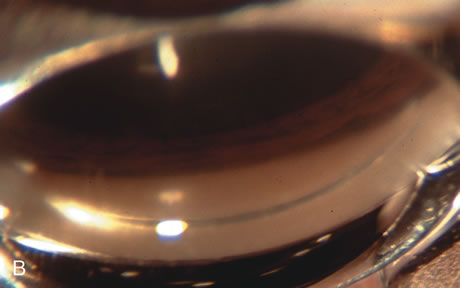

In years past, patients with both cataract and glaucoma frequently provided overwhelming surgical challenges for the ophthalmologist. The ability to carry out phacoemulsification through a 3.2-mm corneal incision along with inserting a foldable IOL is a vast improvement over 11-mm incisions that were common a decade ago (Fig. 1). The anatomical and inflammatory changes to the eye are less with small incision techniques, improving the likelihood of success with concomitant glaucoma surgery. Pharmacologic inhibition of fibrosis along with postoperative wound revision increases the long-term success rate of filtration surgery when combined with lens extraction. (Fig. 2). The learning curve may be steep at times, but the blending of cataract and glaucoma surgical skills slowly falls into place as the surgeon constantly learns and upgrades his or her technique.

Fig. 2. Wound modulation and revision. A. MMC decreases the likelihood of bleb failure in high-risk eyes undergoing combined cataract and glaucoma surgery. Overusage of this potent cytotoxic drug should be avoided owing to a myriad of problems related to the formation of an avascular bleb. B. Office-based laser revision of the operative wound allows for increased postoperative flexibility with less complications. The correct number and tension of scleral flap sutures allows the surgeon to strive for a safe immediate postoperative IOP range. When fibrosis occurs at approximately 1 week, suturelysis or release of sutures increases filtration while avoiding unwanted hypotony.